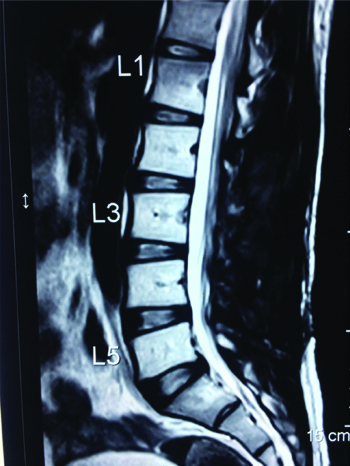

A 25-year-old male patient, a car mechanic by occupation, presented with low back pain for two years with recent onset of left lower limb radiculopathy for three months. On examination, his left SLRT was positive at 30° but otherwise, local examination of the back revealed no abnormality and no focal neurological deficits were observed. Plain radiographs of the lumbar spine showed mild scalloping of the L3 vertebral body. MRI of the lumbar spine revealed an extradural space occupying lesion at the level of L3 vertebral body, which was hypointense on both T1 and T2 weighted sequences, causing compression over the thecal sac and the L3 nerve root on the left side [Table/Fig-1,2].

Preoperative Sagittal T2 weighted MRI showing an extradural space occupying lesion at the level of L3 compressing the thecal sac.